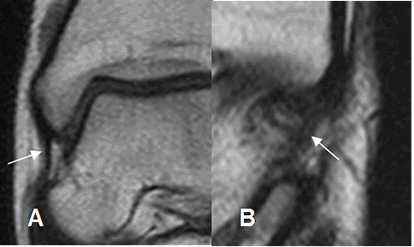

Los ligamentos son estructuras delgadas, con baja señal de intensidad (SI) en todas las secuencia de RM, adyacente a estructuras óseas y rodeados por grasa. (1). (Fig 8 a 17).

En ecografía, los ligamentos son estructuras lineales e hipoecoicas, con un espesor menor a 2 mm. (4). (Fig 9 y 15).

Fig 9. Ligamentos peroneoastragalinos normales en ecografía.

Ligamento peroneoastragalino anterior en A y peroneoastragalino posterior en B.